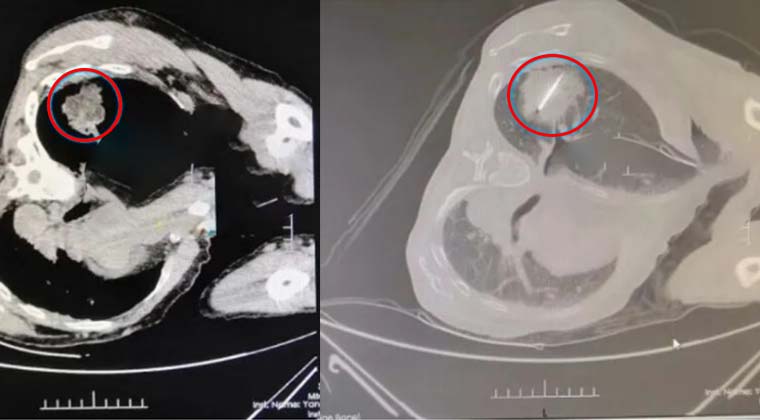

Диагноз: Обнаружено образование в правой верхней доле лёгкого. Проведена перкутанная биопсия, патология и иммуногистохимия показали низкодифференцированный крупноклеточный рак лёгкого (поздняя стадия).

Лечение и предварительные результаты: Комбинированная абляция Kangbo с экстремальными температурами была проведена под визуальным контролем. После процедуры визуализация показала уменьшение размера опухоли и снижения опухолевой нагрузки, что создало благоприятные условия для дальнейшего комплексного лечения и постоянного наблюдения.

Канбо-зонд точно введён в опухолевую ткань под контролем CT в реальном времени.

После двух циклов чередования экстремальных температур большая часть опухолевой ткани подверглась абляции и некрозу.

Кристаллы льда полностью покрывают края опухолевого узла лёгкого.